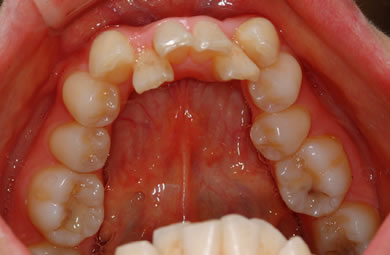

| 主訴 | 上下乱ぐい歯と出っ歯を治したい。 | ||||||||||||||||||||||||||||||||

| 治療方針 | 口元が出ていていること、がたつきが大きいことより、上下左右の第一小臼歯および親知らずを抜歯し、マルチブラケット治療を行う。抜歯した隙間を活用できるよう上顎にはインプラントアンカー(釘)を使用し、その釘より歯を後ろに移動する。 | ||||||||||||||||||||||||||||||||

| 治療内容 | 唇側矯正(シルバー)、矯正用スピードインプラント、ハイブリッドセラミックインレー2本 | ||||||||||||||||||||||||||||||||